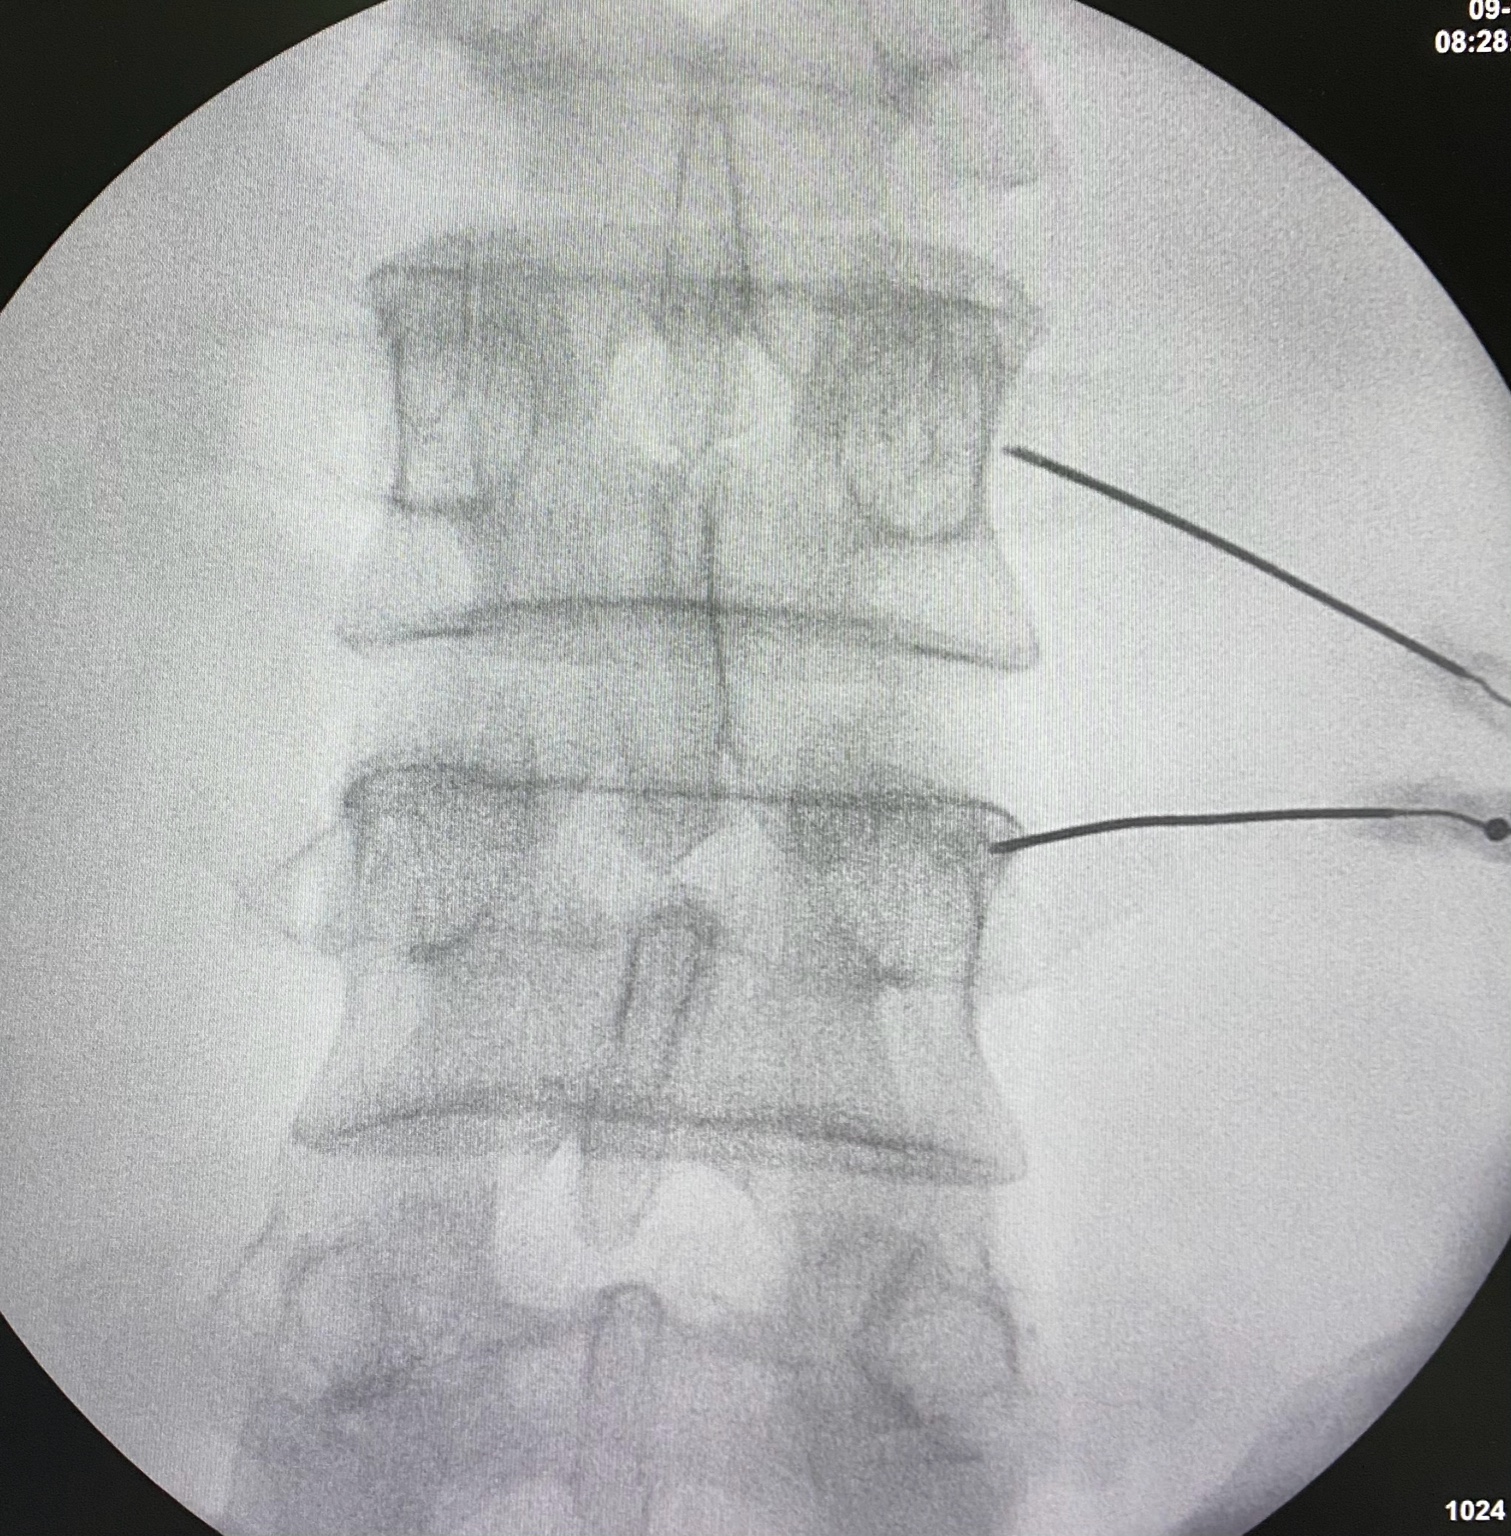

Radiofrecuencia en Columna Lumbar

Indicada para dolor lumbar crónico, causado por artrosis de las articulaciones facetarias. Se aplica sobre los ramos mediales lumbares, bloqueando la transmisión del dolor.

Radiofrecuencia lumbar